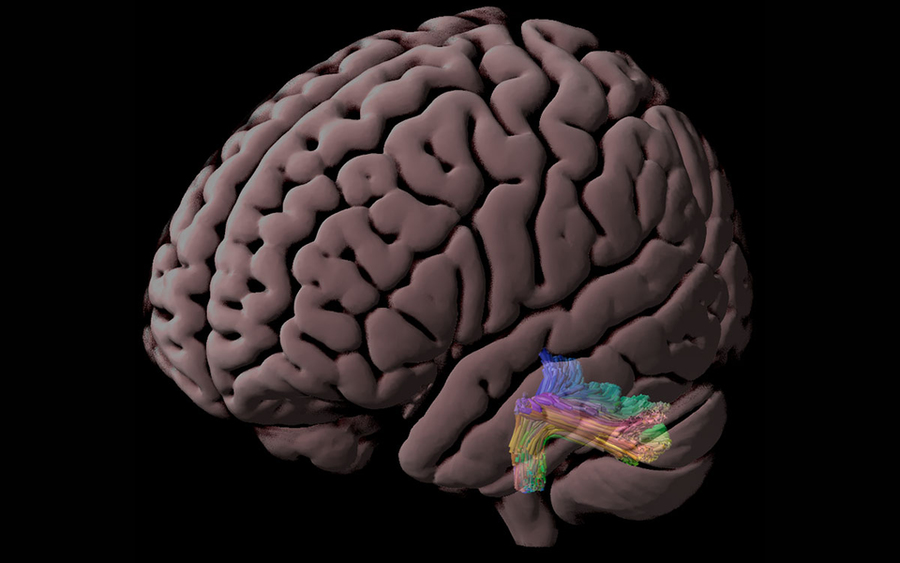

Коннектом мозга: визуализация связей и нейронных путей